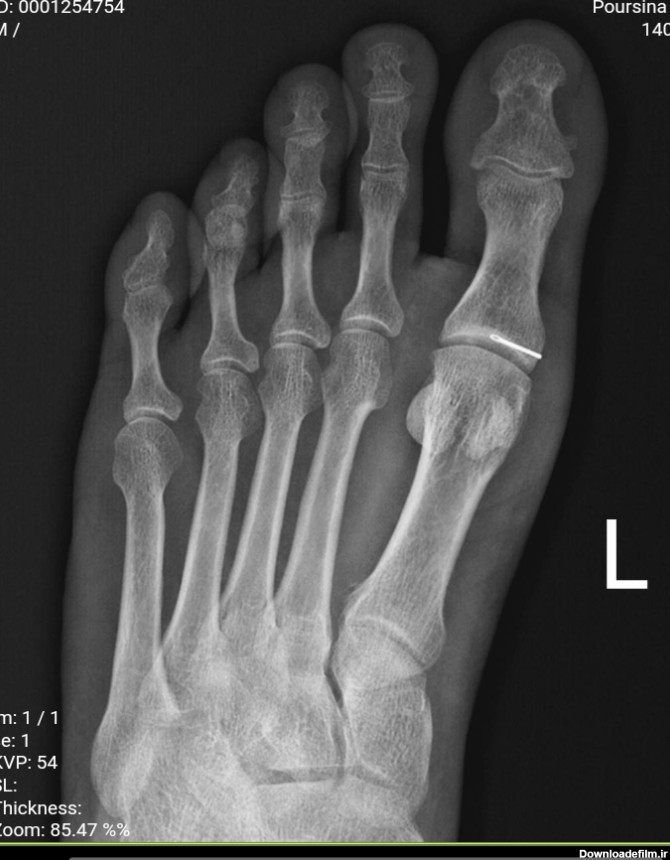

سلام من 2-3 سال پیش تصادف کردم و استخوان ران پام شکست (عکس بالا) قبل تصادف همیشه میرفتم سالن و فوتسال بازی میکردم ... الانم که پام شکسته و پلاتین دارم طبیعتا نمیتونم ... دارم دیوونه میشم 3 ساله فوتبال بازی نکردم و وقتی میرم سالن بازی دوستامو میبینم خیلی ناراحت میشم :((( الان میخوام پامو عمل کنم و پلاتین رو دربیارم که یه سوال دارم ... ⬅️بعد اینکه پلاتینو در آوردم میتونم مثل قبل

سلام دوستان می دانم مثل همه ایرانیها علاوه بر اینکه در زمینه، فوتبال، ورزش و سیاست تخصص دارید در زمینه پزشکی هم تخصص دارید، لطفاً راهنمایی کنید با این سوزن نصفه شکسته شده در پایم چی کار کنم، دکتر ارتوپد گفت نمیخواد عمل کنی درش بیاری، اگر عفونت کرد یا اذیتت کرد بیا دربیار، دیروز ظهر این اتفاق برام افتاد الان کمی درد دارم، شما بگویید چی کار کنم نظر شما صاحب هست😜😜